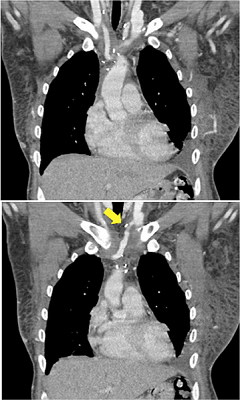

A 17-year-old male patient consulted with us because of a one-year history of facial and right upper limb edema, which were confirmed on physical exam. The patient had had a resection of a mature teratoma two years before and received complementary chemotherapy and percutaneous embolization. He arrived at our clinic with a CT scan showing SVC and brachiocephalic veins obstruction secondary to thrombosis, that was also observed on transesophageal echocardiogram (Figure 4), for which two unsuccessful angioplasties were intended at another institution.